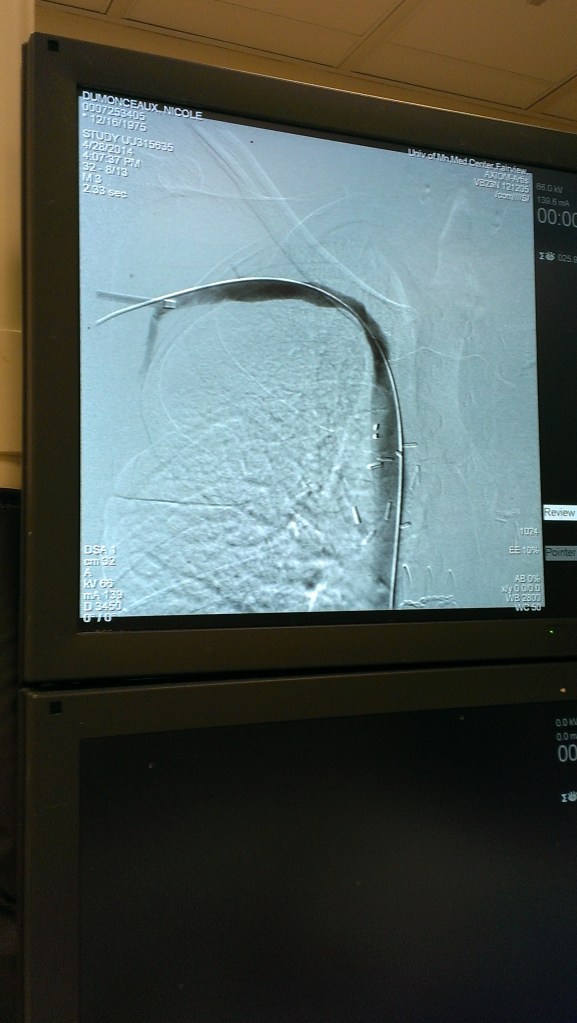

In the first picture below, blood had to travel elsewhere since the main vein was blocked. You can see all the little veins filling because of the blockage. Notice the blood flow stops where it should continue downwards. The second photo shows the flow after the angioplasty. You can see how it is one flowing movement. No more little veins. The blood is flowing as it should. I included the last picture that shows the balloon when it was inflated.